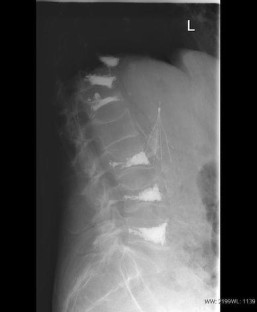

Retrieval of Cement Embolus from Inferior Vena Cava After Percutaneous Vertebroplasty

Percutaneous vertebroplasty is an accepted treatment for painful vertebral compression fractures caused by osteoporosis and malignant disease. Venous leakage of cement and pulmonary cement embolism have been reported complications. We describe a paravertebral venous cement leak resulting in the deposition of a cement cast in the inferior vena cava and successful retrieval of the cement embolus.

Fig. 1